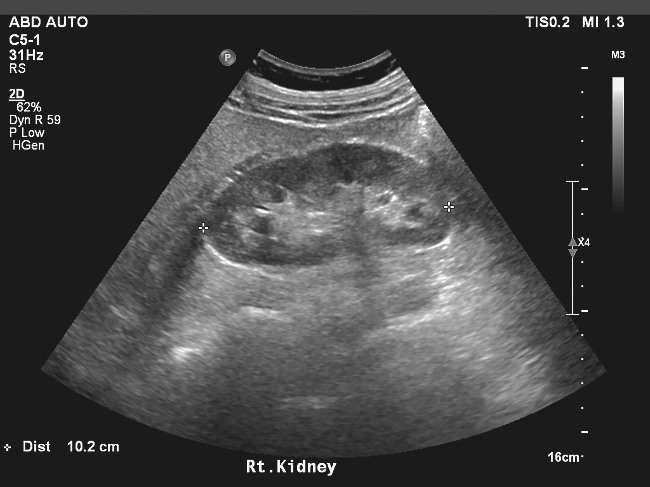

Cosa si vede da un’ecografia ai reni?

L’ecografia renale permette di studiare la morfologia e la struttura dei reni, valutandone dimensioni, forma e posizione. Attraverso questo esame è possibile individuare diverse condizioni:

| Calcoli renali o ureterali | Formazioni iperecogene con cono d’ombra posteriore |

| Cisti renali | Formazioni rotondeggianti a contenuto liquido, semplici o complesse |

| Dilatazione delle vie urinarie (idronefrosi) | Suggerisce un’ostruzione |

| Masse solide o tumori | Richiedono approfondimenti diagnostici |

| Malformazioni congenite | Anomalie strutturali |

| Segni di infezioni o infiammazioni croniche | — |

L’esame consente inoltre di valutare la vescica, verificandone le dimensioni, lo spessore delle pareti e la presenza di eventuali masse o anomalie. Nei pazienti con ipertrofia prostatica, l’ecografia può stimare il volume della prostata e quantificare l’eventuale ristagno urinario dopo la minzione.